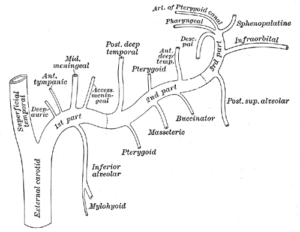

Desde el inicio de su recorrido en la articulación temporo-mandibular, la arteria maxilar entra en la fosa infratemporal del cráneo, un área está formada por los huesos esfenoides, maxilar, temporal y mandibular.

Luego continúa su trayecto hacia la fosa pterigopalatina, donde se relaciona con el músculo pterigoideo lateral, siguiendo un recorrido paralelo a él.

Dado que esta arteria aporta una cantidad considerable de ramas colaterales, se divide su recorrido en tres segmentos para simplificar su estudio anatómico.

Esta división se hace según la relación de la arteria con el músculo pterigoideo lateral. Así, se encuentran los siguientes segmentos:

– Segmento 1: también conocido como segmento óseo. Se ubica en el cuello de la mandíbula. En este pequeño trayecto la arteria da cinco ramas que se encargan de nutrir estructuras internas del cráneo.

– Segmento 2: denominado segmento muscular debido a que en esta parte sigue paralelamente al músculo pterigoideo lateral. Esta sección da cuatro ramos vasculares a estructuras bucales y también es la principal irrigación del músculo pterigoideo lateral.

– Segmento 3: llamado segmento pterigopalatino, es la porción que se encuentra anterior al músculo pterigoideo lateral y da ocho ramos vasculares que se encargan de irrigar el paladar, los músculos de la masticación y la región infraorbitaria.

La arteria maxilar se encarga de irrigar estructuras vecinas de la cara y el cráneo, a través de sus múltiples vasos colaterales.

Estas ramas nutren estructuras tan importantes como la glándula parótida, los músculos de la masticación, las estructuras bucales, nervios craneales e incluso las meninges.